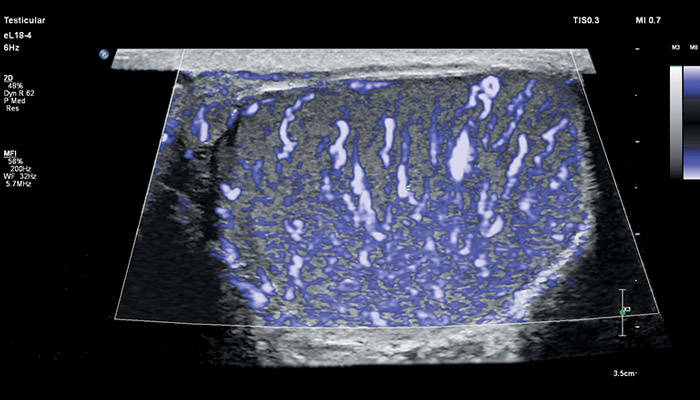

Инновационный датчик eL18-4 работает в частотном диапазоне 2-22МГц, что открывает широкий спектр возможностей его применения в ультразвуковой диагностике. Универсальность датчика позволяет использовать его для комплекса ультразвуковых исследований в таких областях, как: молочная железа (с функцией эластографии сдвиговой волной), поверхностные органы (с функцией эластографии сдвиговой волной), опорно-двигательный аппарат, исследования сосудов (с автоматическим измерением толщины сосудистой стенки), органы брюшной полости, исследования в педиатрии, пренатальная диагностика.

Бесспорное достоинство датчика – его универсальность. УЗ-аппараты, оснащённые eL18-4, помимо акушерства можно использовать для обследования щитовидной железы, молочных желёз, сосудов шеи, рук и ног, органов мужской репродуктивной системы, брюшной полости и малого таза детей и подростков.

Линейный матричный датчик eL18-4 поддерживает режим высокочувствительной визуализации кровотока (Philips MicroFlow Imaging), новый запатентованный метод, который обеспечивает инновационный подход к оценке сосудистого русла. Визуализация MicroFlow преодолевает многие барьеры, связанные с традиционными методами обнаружения кровотока в малых сосудах, обеспечивая высокое разрешение при минимальных артефактах. Метод MicroFlow Imaging поддерживает высокую частоту кадров и качество изображения, применяет инновационные методы сокращения артефактов. Варианты вычитания 2D-изображений, смешивания и параллельного отображения обеспечивают превосходную визуализацию в различных клинических случаях.